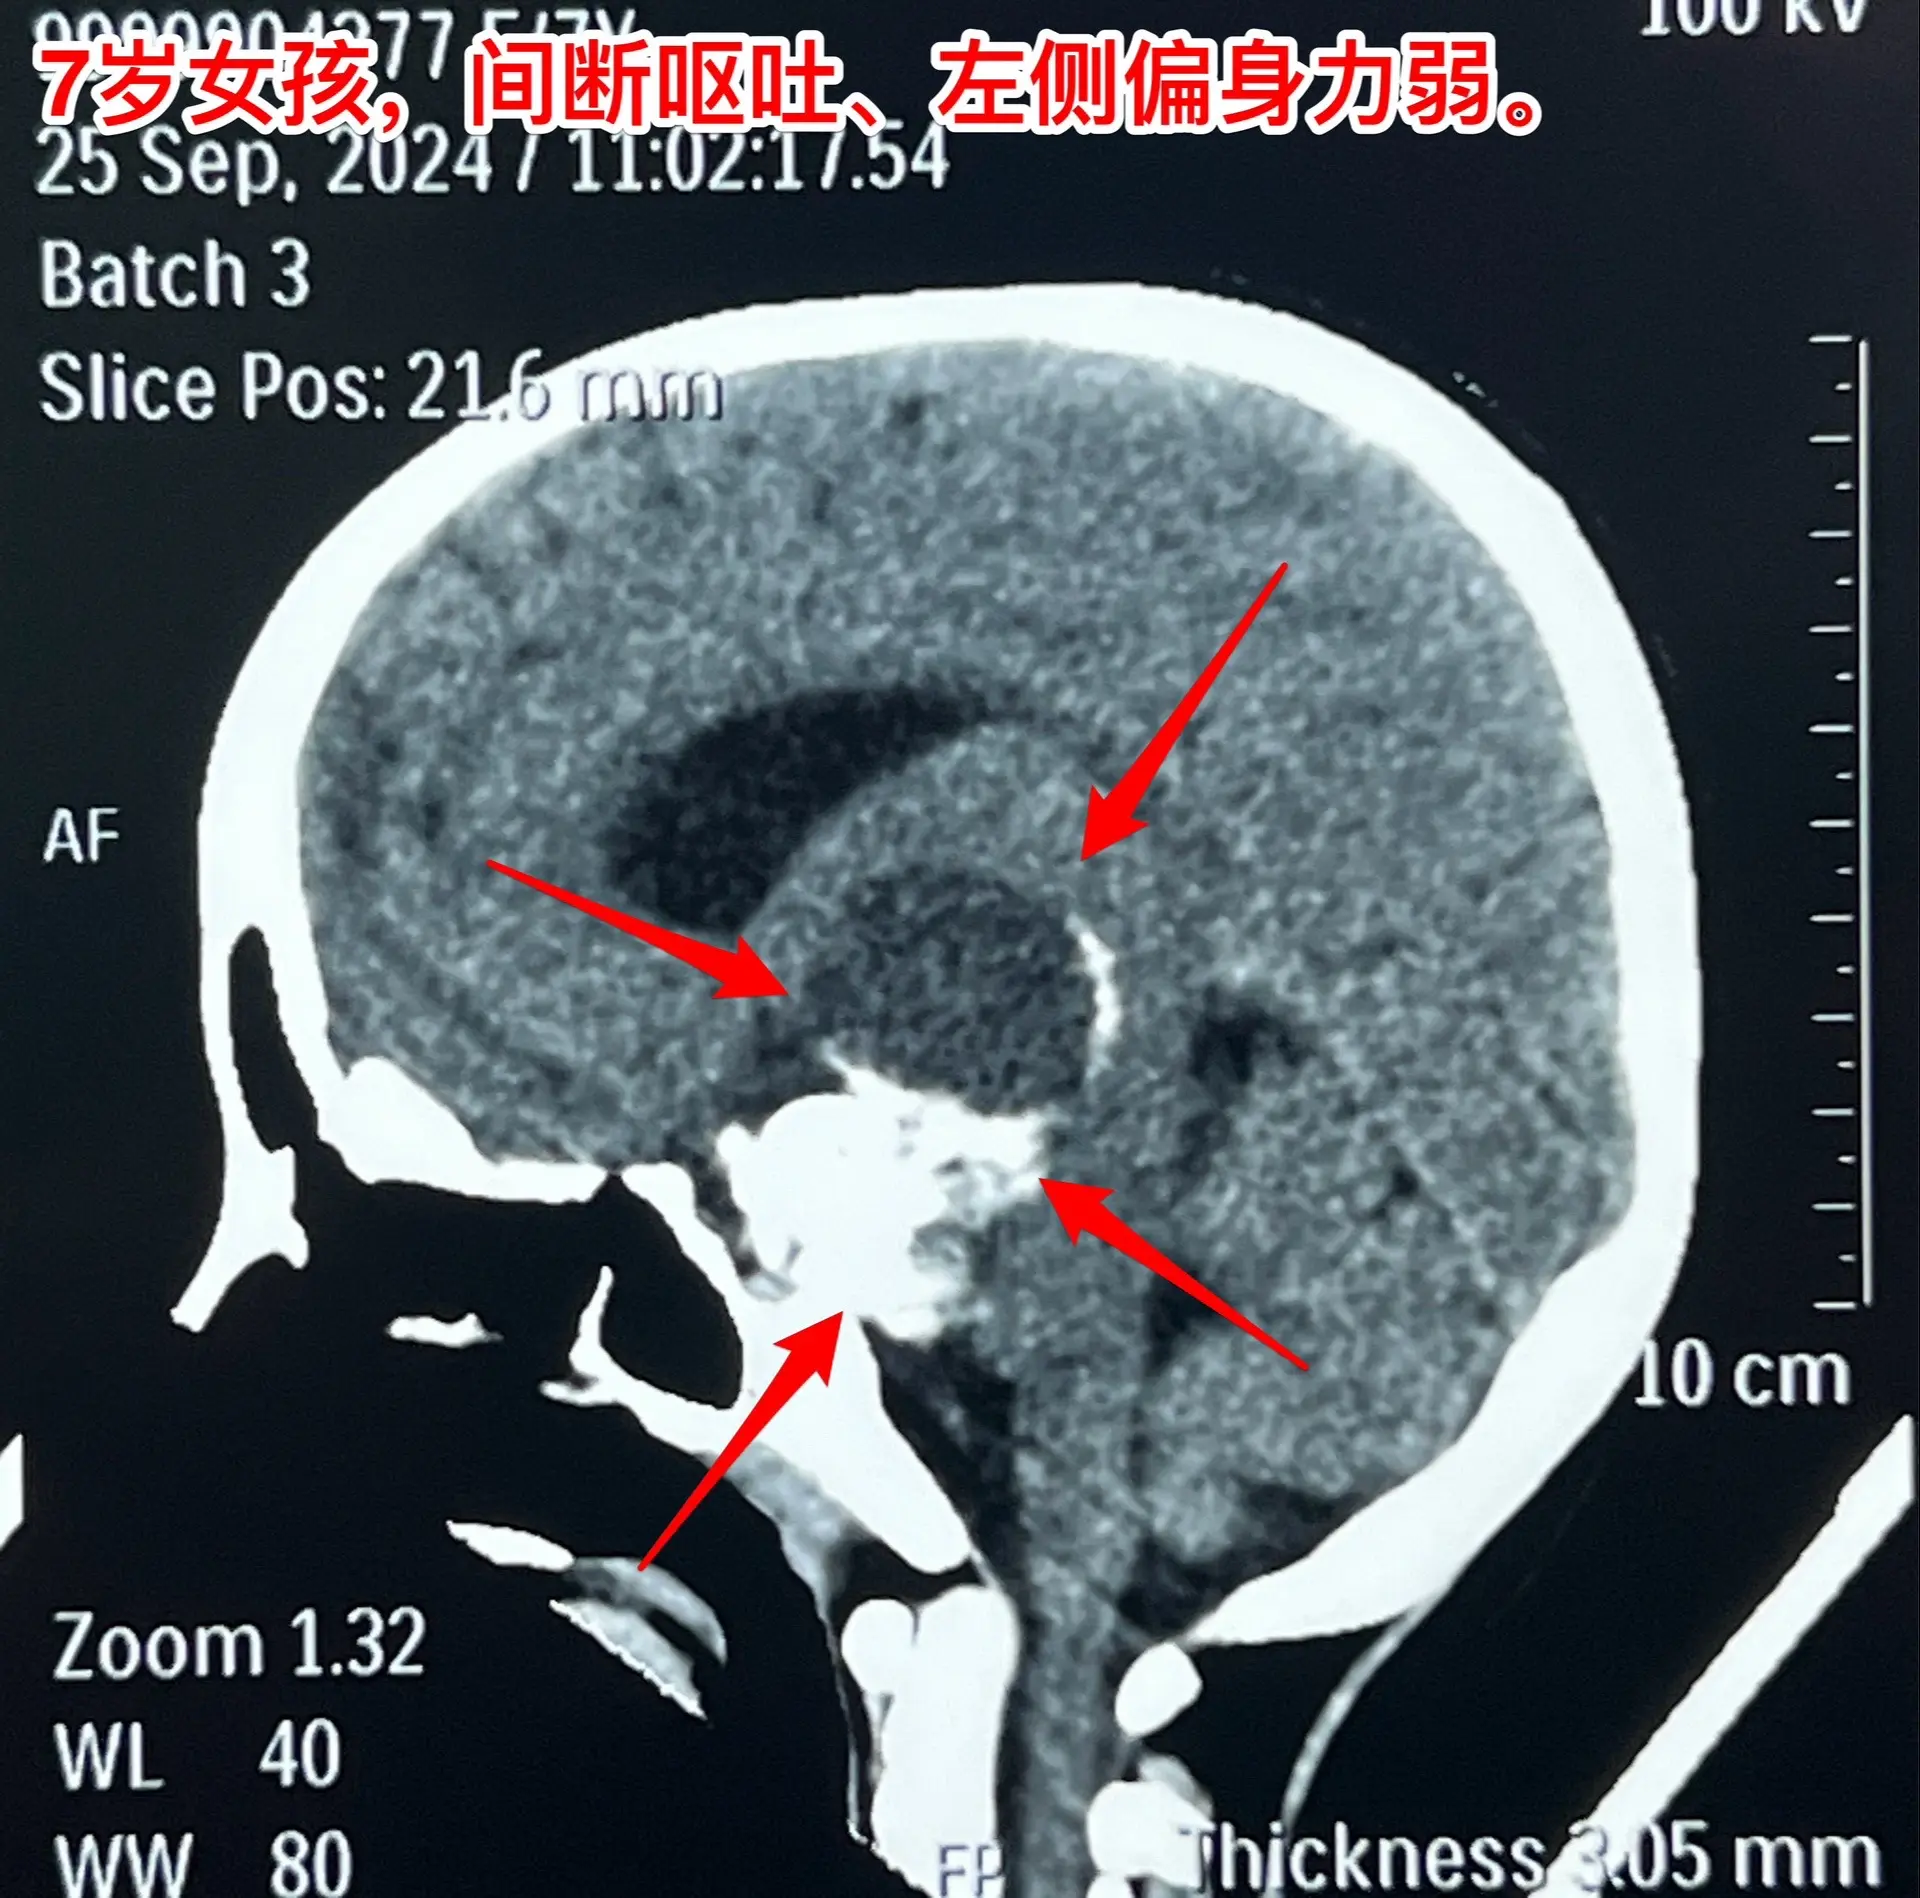

漳州市女孩子脑部长了巨大的颅咽管瘤。7岁漳州市女孩子,入院前两个月经常出现呕吐,按胃肠疾病治疗无效。入院前20天出现左侧上下肢活动力弱,伴有左上肢抖动。在厦门某医院经CT检查发现是脑部肿瘤。 从头CT可以看出这是典型的颅咽管瘤,鞍区有很大的钙化团块,小块肿瘤侵入第三脑室,肿瘤囊向右侧颞部及基底节区生长并有推挤压迫效应。手术有难度啊! 我们的手术入路设计思路:肿瘤起源点在中线,有大块钙化,是手术的难点,故以中线方向为主攻方向,争取将肿瘤的起源点及钙化完全切除!而向右侧颞部生长的肿瘤囊虽然体积大,只是肿瘤的扩张产物,切除的难度并不大,故右侧裂方向只需迂回攻击即可搞定。按这个思路设计手术方案后,手术中也有出乎意料的环节。鞍上的肿瘤钙化块又大又硬,花费很大精力才能将其体积减小,从视交叉前间隙取出。肿瘤囊从颈内动脉下方侵入颞叶,一部分囊自颞部向中线方向返折嵌入到基底节区。如术前所料,这部分囊性肿瘤切除难度不是太大。肿瘤最终得到完全切除,手术后患儿精神好,四肢活动自如。